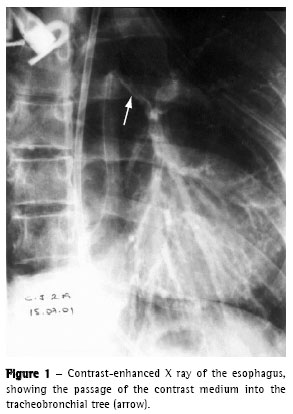

The control chest X ray, after upper digestive endoscopy, revealed left pneumothorax. Left thoracic drainage was performed with immediate lung re-expansion. In the fiberoptic bronchoscopy, we observed an area of destruction of the distal trachea, carina and left bronchus of approximately 3 x 1.5 cm (Figures 2 and 3), as well as exposure of the mediastinal tissue, together with de-epithelization and retraction of the epiglottis and right vocal chord.